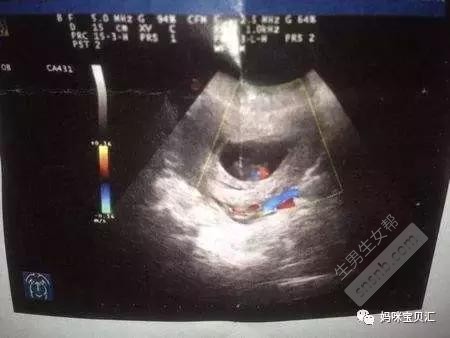

帖子中, 孕妈“未来小天使TA麻”称, 孕囊看男女为什么有的说准,有的说不准,其实是自己不会看数据而已,或者数据时间不合适。如果要看得准,首先数据不能超过8周,40多天是最合适的,然后就是要有3个数据的,“没有3个数据的,一律不能判断,孕囊都是圆柱状的,每个B超师做B超的时候,截面会截取的方位不一样,有的横截面,有的截取竖截面,所以,看图片是长的还是圆的,不能判断男女。”

“如果孕囊成等差数列,比如40*30*20,这样就是女孩,但是如果B超师取了40*20的截面,貌似男孩的数据,结果生出了闺女,造成孕囊看男女不准的说法。”

孕妈“未来小天使TA麻”在帖子中还提醒到,“ 如果只看2个数据的话,推断不了,因为每个B超师获取孕囊的方位不一样,所以不能判断,有3个数据的,是最好判断的,两个数据差不多,第三个数据比前两个小一倍,那肯定是儿子,如果成递减数据就是女儿。还有一种情况就是第三个数据小很多的,比如40*38*10,像10比40和38小很多很多,这个也可能是女儿,但80%还是儿子。”

通过孕囊大小形状是否真的可以推断胎儿性别?对此问题,沈阳市妇婴医院产科门诊主任冯晓静作了回答。冯主任称,孕囊的形状其实是由其张力以及其可伸展的空间来决定的。准妈妈们的孕囊看上去形状有所区别与胎儿性别没有关系。一般发育较好的孕囊是圆扁形的,但是有时孕囊会随宫腔的形状而变长。孕囊的形状由其张力和含羊水量决定的,会自行改变形状。这样,怀孕天数不同,看到的孕囊也可能不一样。另外,每次B 超探头的方向不同,从不同的角度看,孕囊的形状也是不一样的。"所以,将孕囊形状和宝宝性别联系在一起,想象力实在是过于丰富了。孕囊形状看生男生女也是不靠谱的。"冯主任提醒孕妈们,“孕囊看男女其实并没有合理的依据,比起通过B超数值看生男生女,孕妈们还是多把关注点放在胎儿发育情况是否完全正常上面吧。”